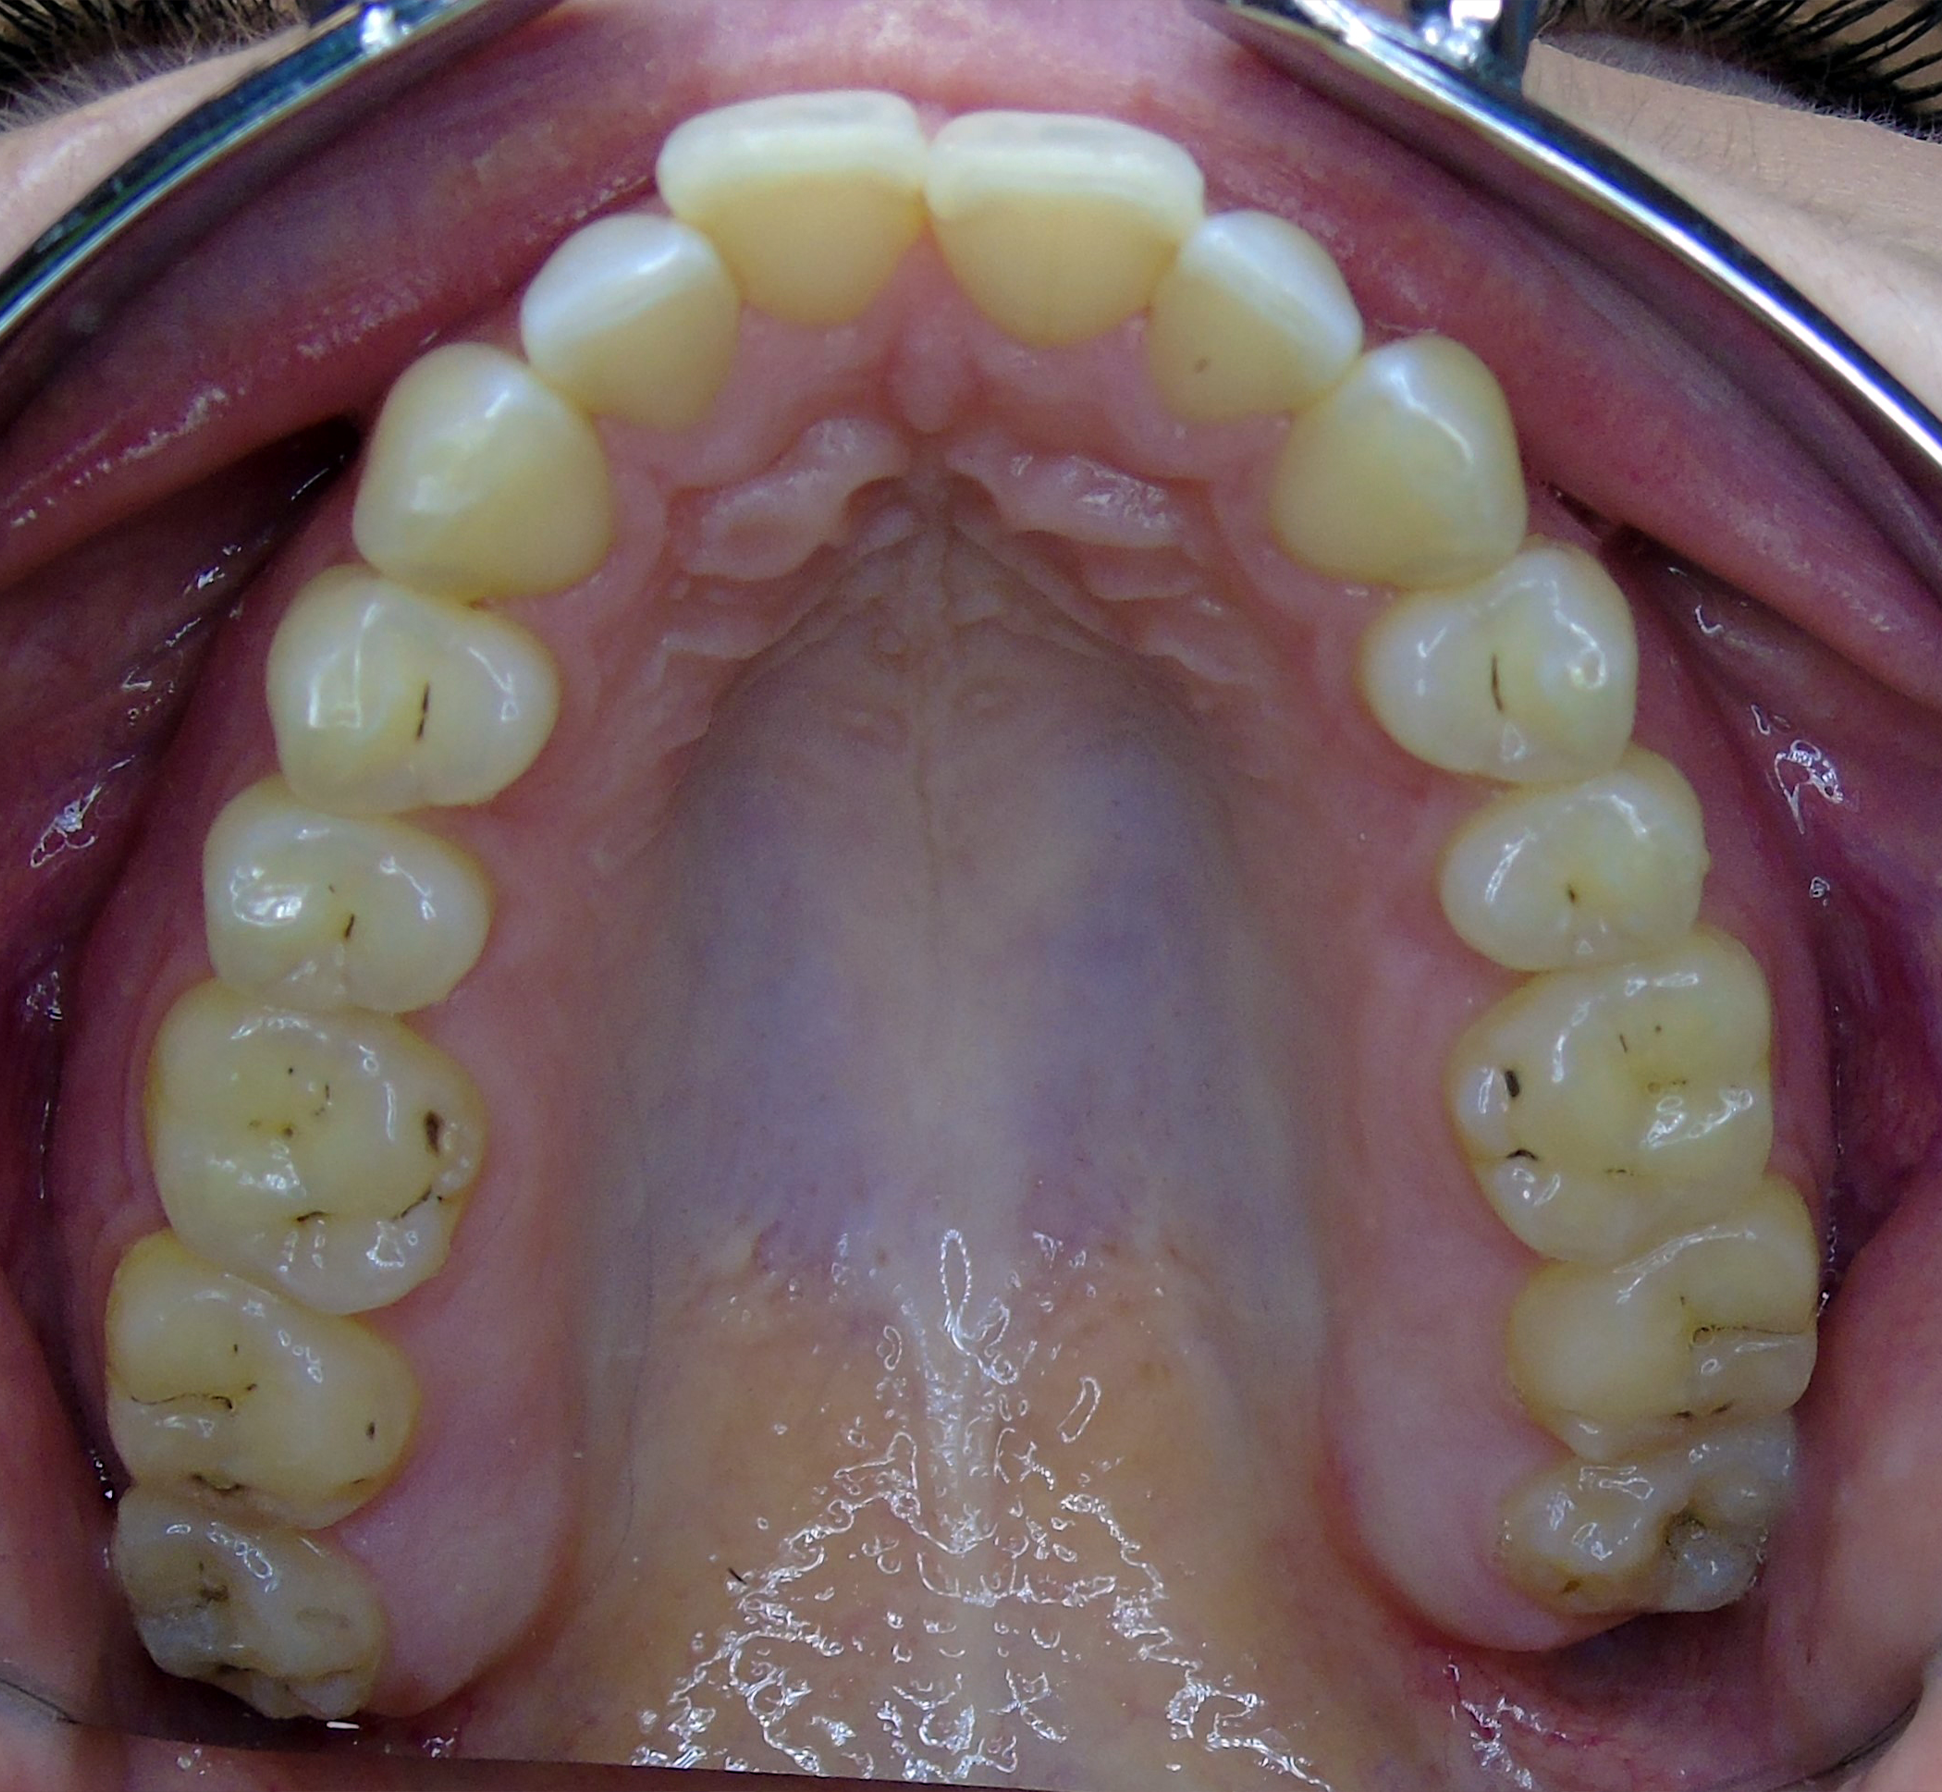

Intraoral evaluation disclosed an Angle class I on both sides, with an anterior open bite (-2.5mm), bialveolar protrusion and mild anterior crowding. Transversally, a narrow upper jaw has been observed. Furthermore, a persistent visceral swallowing pattern and misalignment of the midlines were found.

As can be seen in the images, the planned vertical correction was fully achieved. It has been noticed that Spark™ Clear Aligners have also helped with the patient’s visceral swallowing pattern, by shielding the tongue which then can no longer (unconsciously) rest between the teeth.

The patient was compliant, and the attachments could be removed after four and a half months, as planned. The patient had a total of four appointments and refinements were not necessary. Added to this, no attachments were required on the molars and no elastics were necessary.

Due to the latent tongue dysfunction, the retention of the treatment was completed with both fixed and removable retainers on upper and lower arches, to ensure the final result of the treatment. Six months after the treatment, the result is still stable.